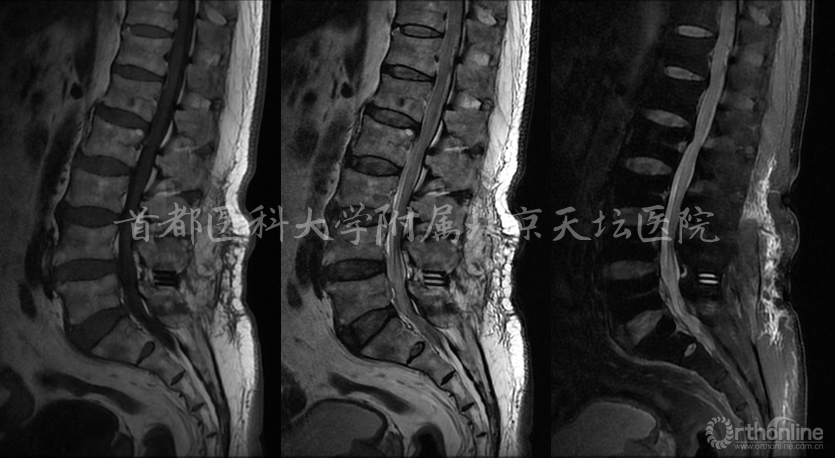

影像资料: